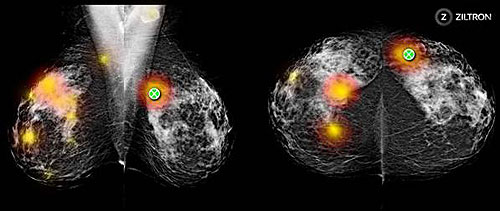

Ảnh chụp màn hình của bản đồ nhiệt